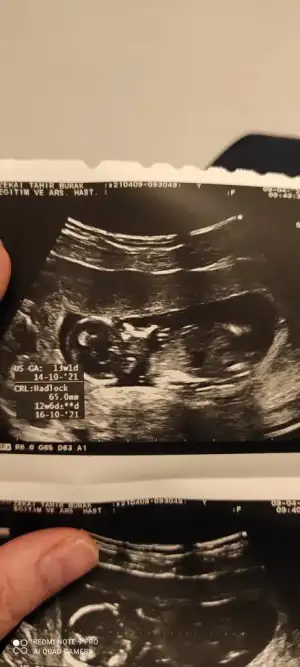

dr soylemeden siz gorun genital nub teorisi ( bebegin cinsiyeti)

Ikra meyra Ikra meyra canim 12+2 bı tahmin de bulunurmusun.İlk bebeğimi bilmistin ya.bunada yorum yaparsan sevinirim.tesekkurler .

Teşekkürler canim Dr ilk erkek gb ama kız diyorum dedi benimki ters çıkıyorda dedi 😄😄.hayırlısı inşaallah demekki bir oğlum daha olacak .hayırlısı artık.

E emrsu bakalım ne çıkacak o kesin konuşmaktan çekindi biraz ilerleyen aylarda söyleyelim dedi.😊